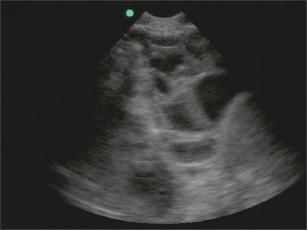

Complex pleural effusions have internal echoes that may be diffusely distributed within the fluid or may be in a septate pattern (Figure 3). A complex septate pattern is caused by fibrin strands in the fluid and may indicate a complicated parapneumonic effusion, empyema,m or hemothorax, but it does not necessarily indicate loculation.

Figure 3 –

Complex pleural effusions may occur in a septate pattern, as seen here, or they may be diffusely distributed within the fluid. A complex septate pattern is caused by fibrin strands in the fluid and may indicate the presence of a complicated parapneumonic effusion, empyema, or hemothorax, but it does not necessarily indicate loculation.